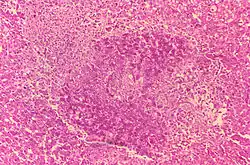

Beim Eintritt des Erregers über die Schleimhäute (z. B. oberer Verdauungstrakt oder Respirationstrakt) kommt es zu einer uncharakterisierten und unspezifischen Entzündungsreaktion. Nach der Phagozytose des Erregers durch Granulozyten, in denen sie überleben können, werden sie durch die Granulozyten in die lokalen Lymphknoten transportiert. Von dort kann sich Brucella über das Blut (hämatogen) weiterverbreiten und im Organismus streuen. In befallenem Gewebe versucht der infizierte Organismus durch die Bildung von typischen, nichtverkäsenden Granulomen die Erreger zu isolieren und die weitere Infektion zu begrenzen.

Weitere Organmanifestationen sind in 10 % urogenitale Entzündungen, z. B. eine Hodenentzündung. In weniger als 2 % entsteht eine Herzklappenentzündung. Sehr selten sind eine Hirnhautentzündung oder eine Lungenentzündung. Die lokalen Entzündungen sind in der Regel granulomatös und können denen bei einer Tuberkulose ähneln.